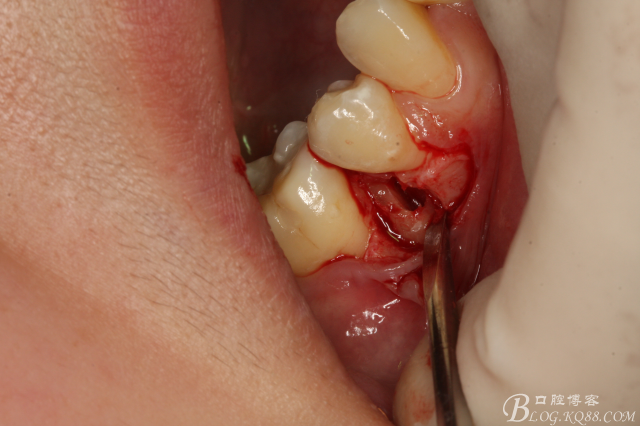

圖12.微創(chuàng)牙挺放入制備好的溝槽內(nèi)。

圖13.取出一塊牙根。給余留 牙根騰出脫位空間

圖14.緩慢在余留牙根周圍用挺,挺松45余留牙根